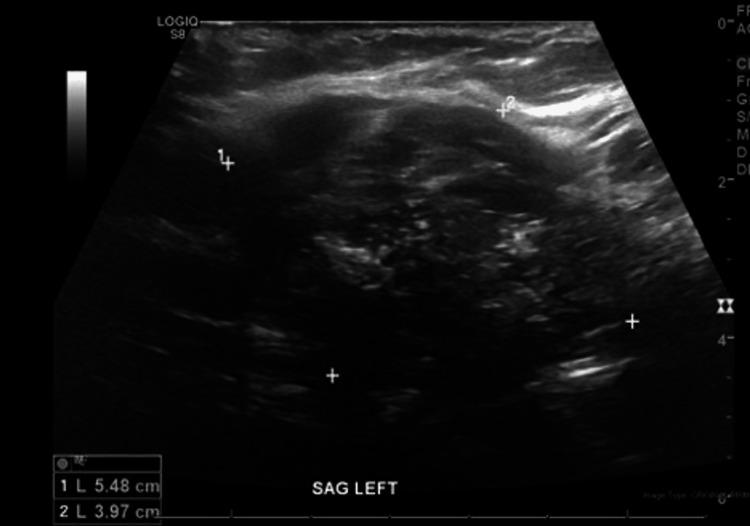

Recurrent Metastatic Colorectal Adenocarcinoma to the Thyroid Gland Presenting With Vocal Cord Paralysis and Inspiratory Stridor.

The most common sites for metastases of colorectal cancer include the liver, lungs, brain, and regional lymph nodes. However, a limited number of reported cases describe colon cancer metastasis to the thyroid gland. Metastatic colorectal adenocarcinoma to the thyroid gland is rare. The majority of these cases with colon cancer metastases to the thyroid gland are diagnosed years after initial treatment of colon cancer. The discovery is usually made after routine surveillance imaging, and often patients have minimal or absent symptoms. We report a case of a recurrence of metastatic colorectal adenocarcinoma to the thyroid gland presenting with vocal cord paralysis and inspiratory stridor.

结直肠癌最常见的转移部位包括肝脏、肺、脑和区域淋巴结。然而,仅有少数报道病例描述了结肠癌转移至甲状腺。甲状腺转移性结直肠腺癌较为罕见。这些结肠癌转移至甲状腺的病例大多在结肠癌初始治疗数年之后才得以诊断。通常是在常规监测成像后发现,而且患者往往症状轻微或无症状。我们报告一例甲状腺转移性结直肠腺癌复发的病例,该病例表现为声带麻痹和吸气性喘鸣。